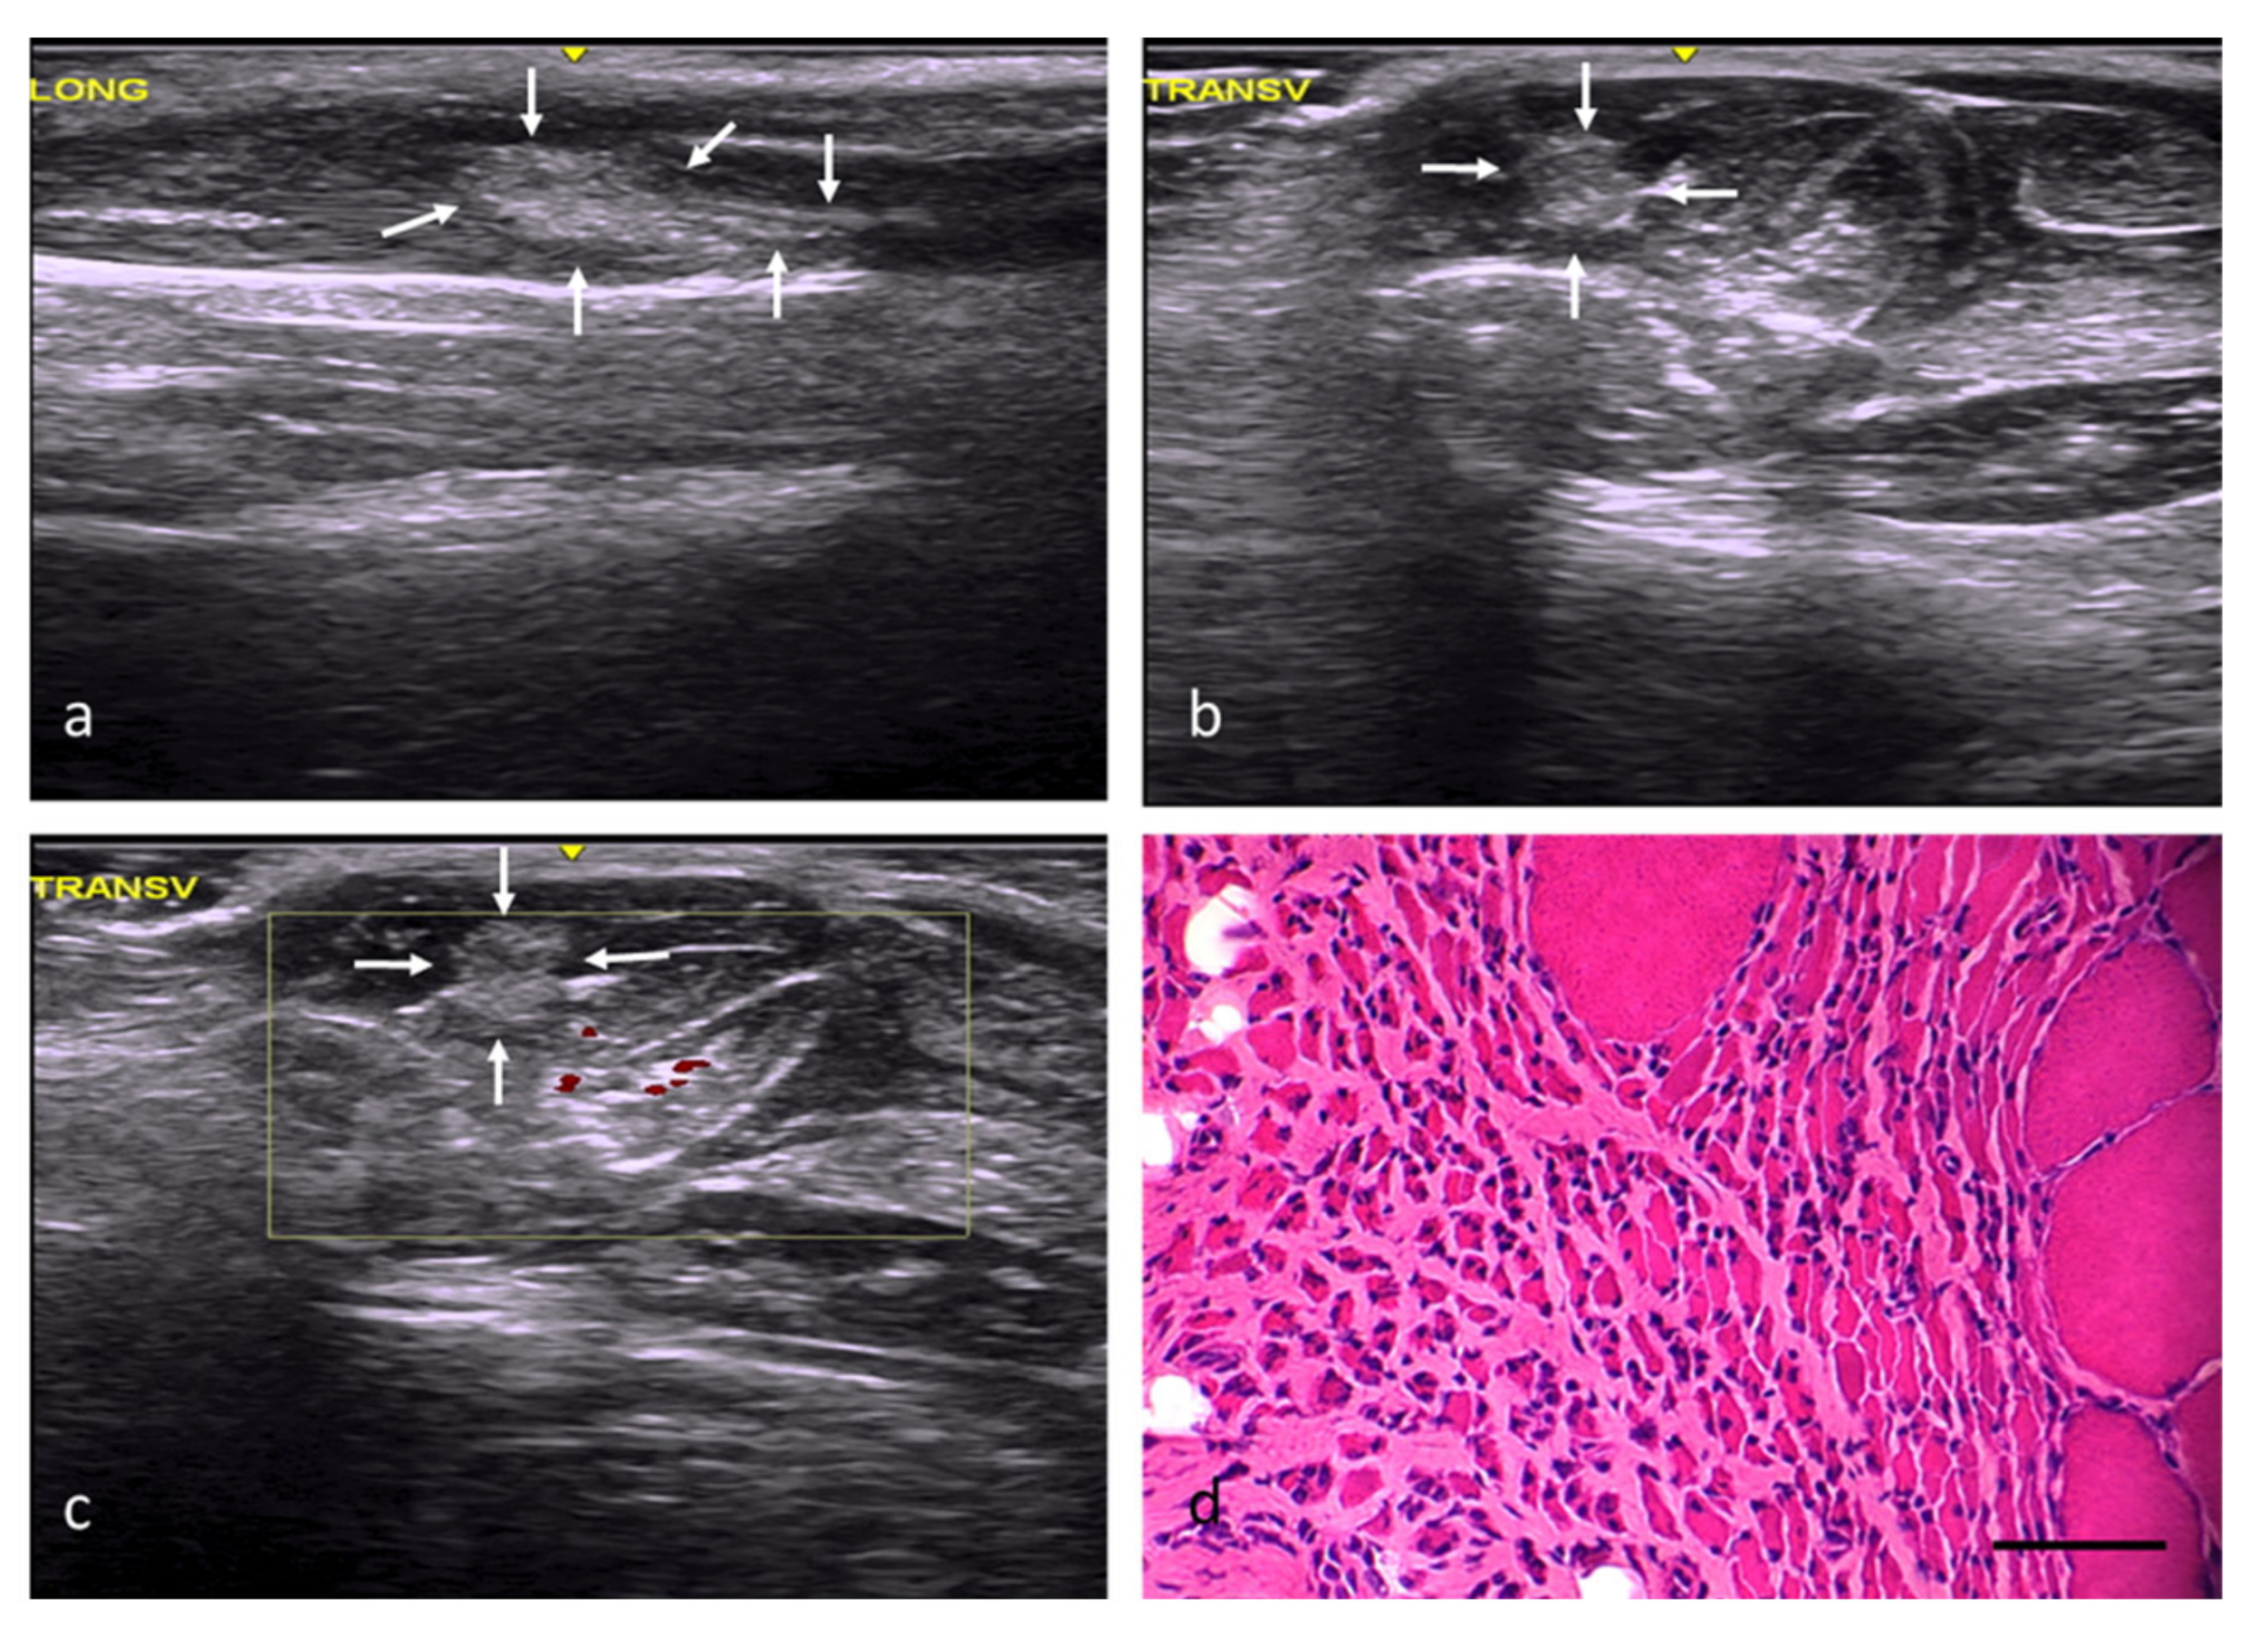

Figure 6.

DM group. (a) Longitudinal axis, with images of an injury with increased echogenicity and a distorted echostructure compared with the adjacent muscle tissue. (b) Transverse axis, with images of a well-defined, oval injury with increased echogenicity. (c) Transverse section assessed by power Doppler imaging, with images of a slight, predominantly peripheral, increase in intralesional vascularization. (d) Transverse section representative of the muscle histology. H-E. Size scale: 100 µm.

In the DM group, the decellularized matrix implantations resulted in significant fibrosis (68%), with a very scarce number of newly formed, small, and overall disoriented fibers (Figure 6d) (Table 2). In addition, foci of a chronic inflammatory infiltrate with multinucleated giant cells were found among of the fibroadipose tissue.